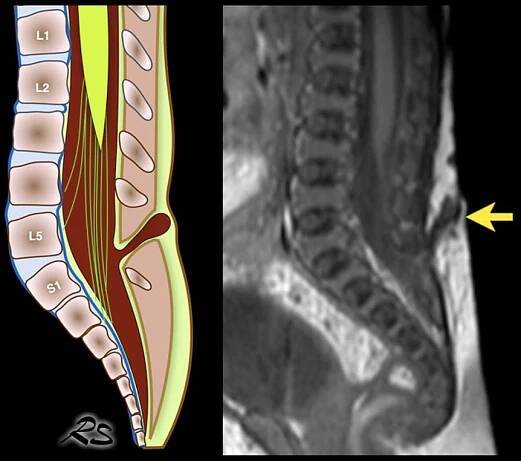

Spina bifida (SB; / ˈ s p aɪ n ə ˈ b ɪ f ɪ d ə/; [9 ] Latin for 'split spine') [10 ] is a birth defect in which there is incomplete closing of the spine and the membranes around the spinal cord during early development in pregnancy. [1…

Spina bifida, někdy též obecně označovaná jako „rozštěp páteře“, je vrozená vada (VV) CNS ze skupiny rozštěpů neurální trubice (neural tube defects; NTD).

„Rozštěp páteře, odborně nazývaný spina bifida, je vrozenou vývojovou vadou centrální nervové soustavy (CNS). Tato vada patří do skupiny rozštěpů neurální trubice a postihuje část páteře mezi bederními a křížovými obratli.

Spina bifida , často nazývaná rozštěp páteře, je vrozená vada, která se vyskytuje, když páteř není úplně uzavřená během embryonálního vývoje.